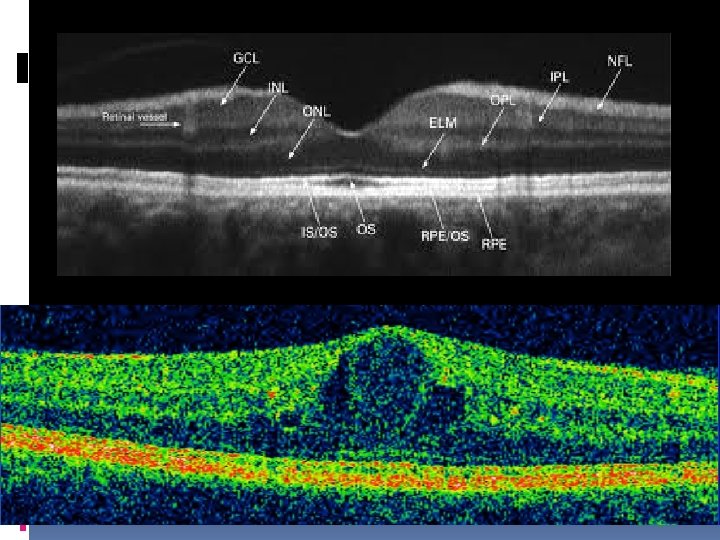

What is diabetic retinopathy